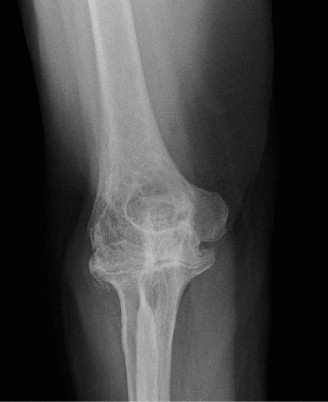

The pathological cascade in RA begins with synovial inflammation (synovitis), characterized by pannus formation, which invades and erodes articular cartilage and subchondral bone. This process, driven by inflammatory cytokines and proteases, leads to joint space narrowing, subchondral cysts, marginal erosions, and ultimately, osteolysis and capsular laxity. The typical presentation includes pain, swelling, stiffness, and progressive loss of motion, frequently progressing to fixed flexion deformities, valgus instability (due to radial head erosion and lateral collateral ligament attenuation), or less commonly, varus deformity. The ulnar nerve is particularly vulnerable to compression or traction neuropathy due to cubital tunnel involvement, tenosynovitis, or valgus deformity.

In RA, the synovial hypertrophy and effusion can directly impinge on nerves. Furthermore, bony erosions and progressive deformity can alter normal anatomical relationships, making surgical dissection more challenging. The radial head is frequently involved, leading to erosions and osteolysis, often resulting in radial head subluxation or dislocation and contributing to valgus instability. The olecranon and coronoid fossae can also undergo significant erosion, leading to bone loss.

The pathophysiology involves sustained synovial inflammation (pannus formation) that erodes articular cartilage, subchondral bone, and ultimately compromises ligamentous integrity. This leads to characteristic radiographic changes including joint space narrowing, subchondral cysts, marginal erosions, and osteopenia. Over time, these changes result in significant bone loss, joint subluxation, and debilitating deformity. The ulnar nerve is particularly vulnerable to compression or traction neuropathy due to synovitis, effusions, or progressive valgus deformity.

In RA, the articular surfaces of all three joints can be severely eroded. The radial head frequently undergoes significant osteolysis and erosion, leading to radial head subluxation or dislocation and contributing to valgus instability. The trochlear notch of the ulna and the olecranon process can also be significantly eroded, resulting in bone loss that complicates implant fixation during arthroplasty.

* Progressive joint destruction and deformity: Evidenced by advanced radiographic changes such as severe joint space narrowing, extensive erosions, subchondral cysts, significant osteolysis, or joint subluxation/dislocation. Common deformities include fixed flexion contracture (>30-45 degrees), severe valgus instability, or less commonly, varus deformity.

- Plain Radiographs: Anteroposterior (AP) and lateral views of the elbow are fundamental. Obtain true AP and lateral projections. Evaluate for characteristic RA changes: diffuse joint space narrowing, articular erosions (radial head, capitellum, trochlear notch, olecranon), subchondral cysts, osteopenia, and joint subluxation or dislocation. Assess overall bone stock, particularly at the distal humerus and proximal ulna, which is crucial for implant fixation. Stress radiographs may be considered to evaluate ligamentous instability if not readily apparent clinically.

- Computed Tomography (CT) Scan: Highly recommended for advanced RA elbows, especially in cases with significant bone loss, complex deformities, or revision surgery. CT provides detailed three-dimensional information on bone morphology, the extent of erosions, and medullary canal dimensions, facilitating accurate pre-operative templating for implant size and position. It helps identify potential challenges for fixation and informs decisions regarding bone grafting or custom augments.